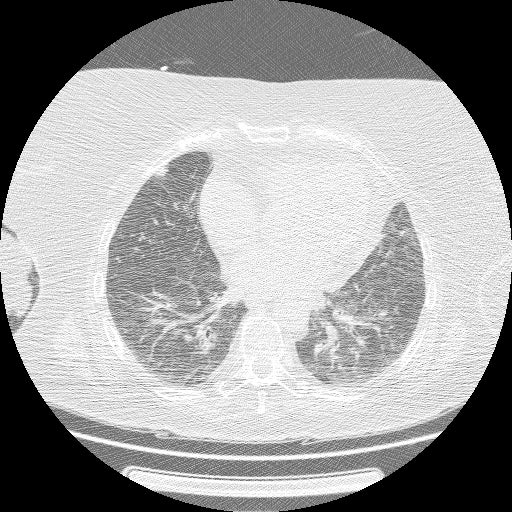

【EIRL Chest CTによる表示例】

① 標準線量CT